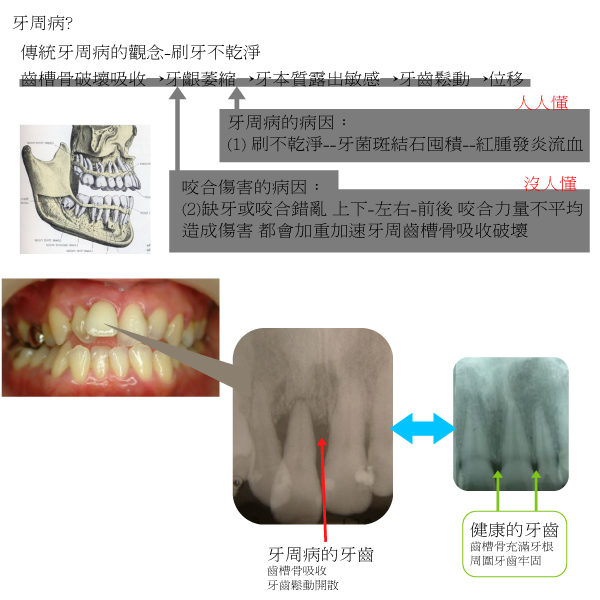

成人和老年人口腔疾病情況,常常不像年青人簡單的蛀牙補洞,大多數都存在嚴重的牙周病,牙齒動搖、拔除、牙齒移位殘缺和牙床萎縮肌力弱化等問題。

治療可能同時需要根管治療和牙周病科、義齒科、矯正科、植牙科等不同專科醫師協同診斷和各科流程管控(統合治療),

才能得到最佳最速的效果。